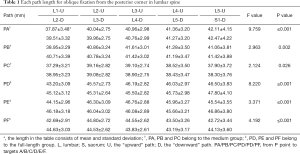

The lengths of each path (Table 1)

Full table

In the medium group, PC path was the shortest (38.56±3.25 mm), PA path and PB path had little difference (P=0.123), and there was no statistical significance. In the full-length group, PF path was the shortest (43.86±3.09 mm), and there was no significant difference between PD path and PE path (P=0.177) (Figure 10). All the paths increased successively from L1 to S1, among which PA and PD paths were the most obvious, followed by PB and PE paths. PC path and PF path first increased and then decreased (Figures 11,12).

In this article, we preset six paths as screw trajectory of oblique fixation from posterior corner in lumbar spine, namely, PA, PB, PC, PD, PE, and PF (Figures 3,4). The design of the pathway is determined by the technical characteristics of spinal endoscopy in clinical practice, considering simultaneously the biomechanical properties of the screw, the longer bone canal and more cortical penetration. The paths should be neither penetrating into the intervertebral space nor making the anterior large vessels injured. Considering the above factors, PE path should be the optimal (longest) path for oblique fixation from posterior corner in lumbar spine.

PE path was the longest in all the paths for oblique fixation from posterior corner in lumbar spine, with an average length of 45.95 mm, which was significantly longer than other paths in the same vertebral body (Figures 10-12). Its upward path first increases and then decreases, reaching the highest point at L3 (46.76±2.88 mm). Its downward path first decreases and then increases, with the lowest decline at L5 (45.66±3.21 mm) (Figure 20). At the same time, the fixed angles (a2, b2, c2) of the PE path in sagittal and axial planes are between a1-a3, b1-b3, and c1-c3, which may neither penetrate into the intervertebral space nor injure the anterior large vessels. Therefore, the PE path is safe and easy to grasp in theory.

In addition, the pullout strength of PE path is greater because the bone canal was across the entire vertebral body from the posterior (upper and lower) corner of one side in lumbar spine oblique to the anterior (lower and upper) corner of the contralateral side in lumbar spine. The PE path is considered to be the optimal one for oblique fixation from posterior corner in lumbar spine.